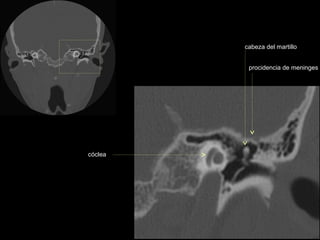

cabeza del martillo

procidencia de meninges

cóclea